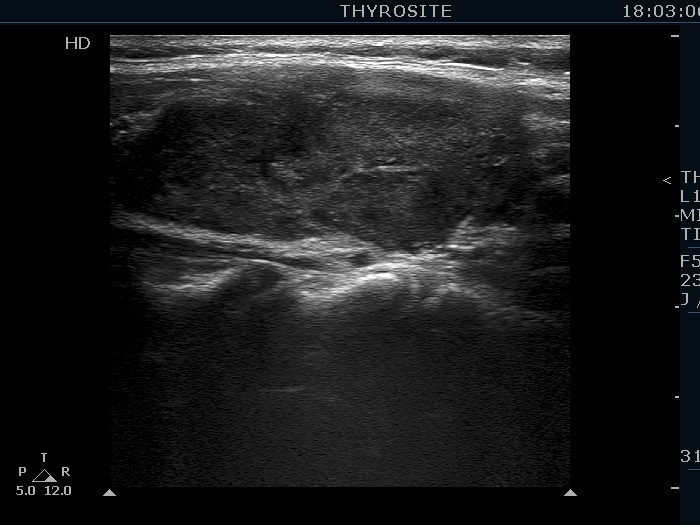

Lymphocytic thyroiditis - case 786

Second examination 19 months after first visit (ultrasonographic picture 5)

Left lobe, longitudinal scan. The echogenicity index in this section is around 70%.